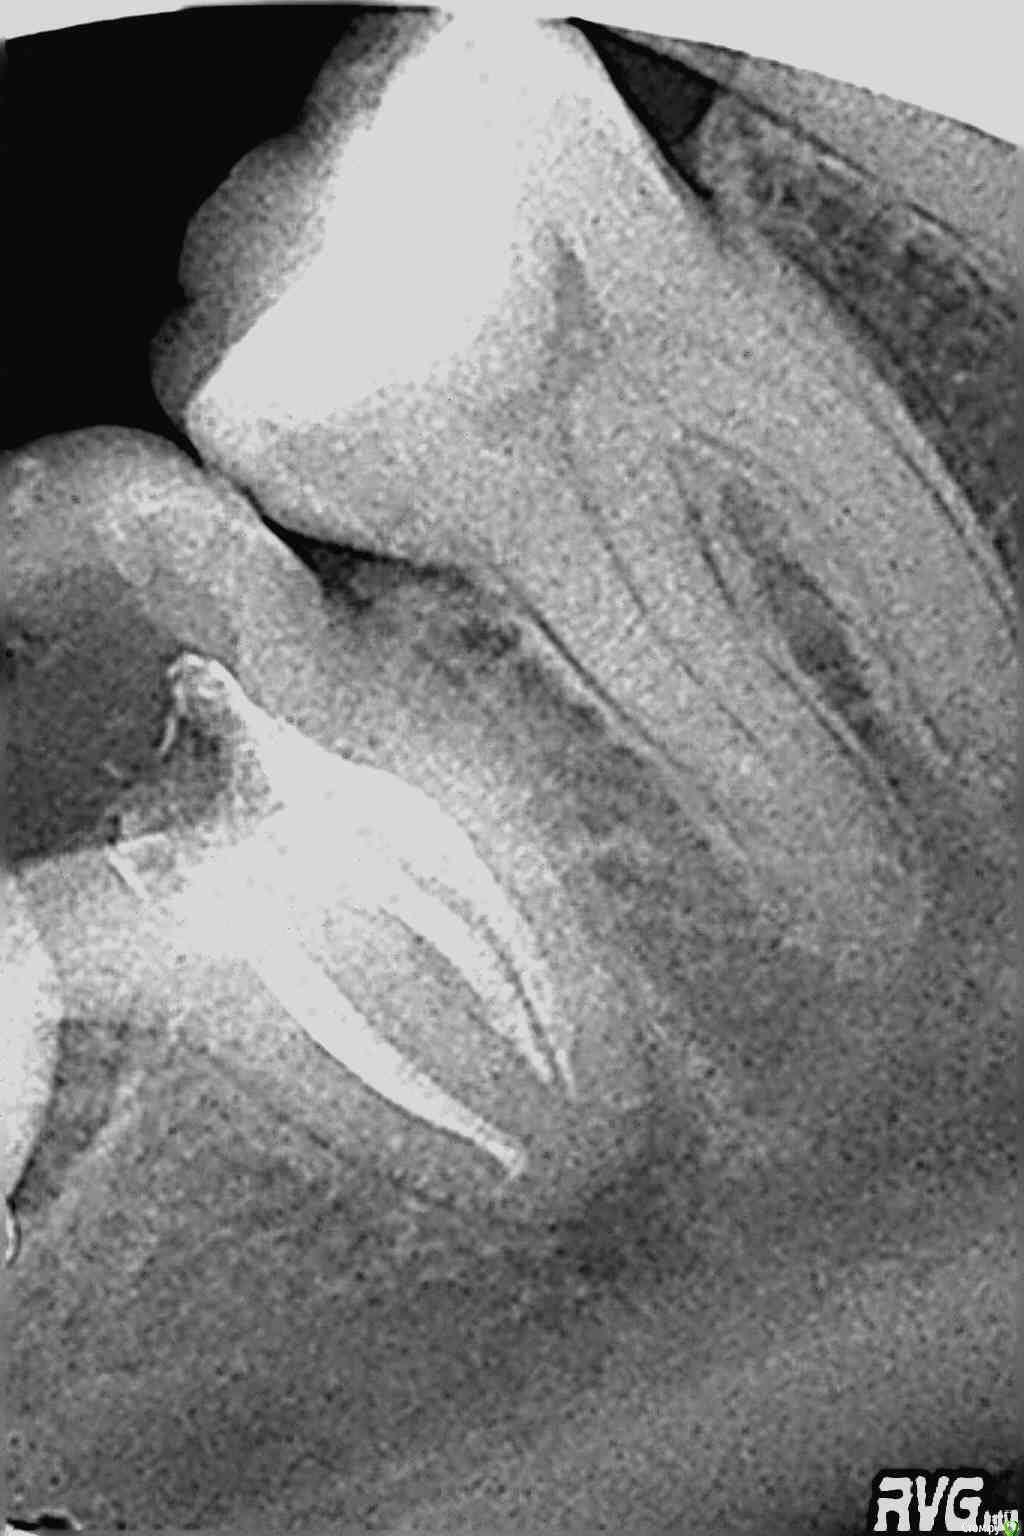

ZubFairy Опубликовано 3 апреля, 2014 Поделиться Опубликовано 3 апреля, 2014 (изменено) Уважаемые доктора,каков Ваш план лечения таких зубов 46,47? Изменено 3 апреля, 2014 пользователем ZubFairy 1 1 Ссылка на комментарий

ZubFairy Опубликовано 3 апреля, 2014 Автор Поделиться Опубликовано 3 апреля, 2014 Фото плохого качества,если получится перефоткаю . Оба зуба не беспокоят.Мой план лечения:перепломбировка каналов в 46,пломба ,коронка . А вот с 47 сложно. На данный момент он пациента не беспокоит,но 2 недели назад были сильные боли на фоне простуды. Сейчас всё ок,перкуссия и пальпация безболезненны. Эндомотора у меня нет,файлы обычные,гутта ассорти,эндометазон.(и так на 250 км.вокруг),поэтому послать к другому доктору не получится. Скажите свой план лечения таких зубов? Ссылка на комментарий

Kivilgar Опубликовано 3 апреля, 2014 Поделиться Опубликовано 3 апреля, 2014 А там на снимках это дефекты пленки в виде трещин или что это? Ссылка на комментарий

ZubFairy Опубликовано 3 апреля, 2014 Автор Поделиться Опубликовано 3 апреля, 2014 В виде трещин это каляки -маляки рентгенолога,пишет какие-то свои знаки всегда на нужных зубах. Ультразвука с эндочаком нет,на удаление пациент не пойдет:не болит же,будет тянуть его до конца. Вот и спрашиваю,как его лечить и чем,могу купить ручные профайлы,в каналы что то другое кроме эндометазона . Сразу пломбировать нельзя,надо что то ещё в каналы положить на какое то время,потом рентген контроль и тогда уж..? Ссылка на комментарий

Kolchanov Опубликовано 5 апреля, 2014 Поделиться Опубликовано 5 апреля, 2014 Почему семерку-то все приговорили? Что там с ней? По этим снимкам вообще ничего нельзя сказать Ссылка на комментарий

ger_berra Опубликовано 5 апреля, 2014 Поделиться Опубликовано 5 апреля, 2014 Почему семерку-то все приговорили? Что там с ней? По этим снимкам вообще ничего нельзя сказатьЯ согласна на счёт качества снимков,но мне не нравки тень в бифуркации в твердых тканях. Ссылка на комментарий